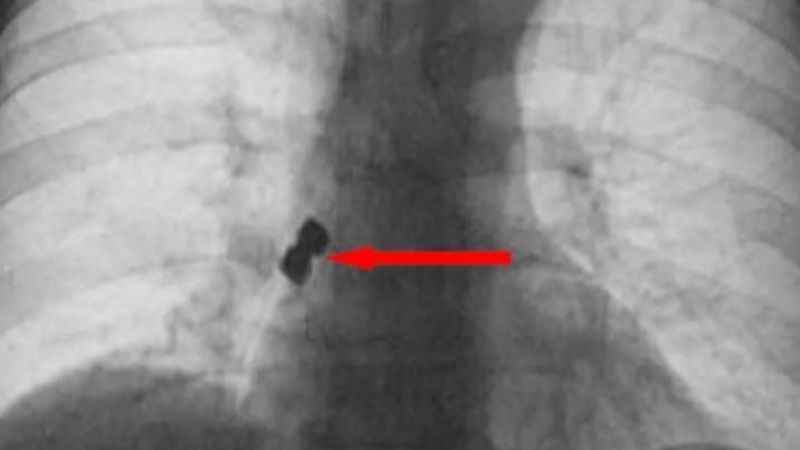

Operasyon esnasında birbirine yapışık halde olan 2 adet implant bir anda hastanın dişinden düştü. İmplantlar ardından hasta yutkununca akciğerlere kaçıp sağ nefes borusunu tıkadı. Nefes almakta zorlanan D.K., ardından Emirdağ Devlet Hastanesi’ne kaldırıldı. Burada yapılan müdahalenin ardından D.K., Afyonkarahisar kent merkezindeki bir hastaneye sevk edildi. Burada D.K.'nın akciğerine kaçan implantlar cerrahi operasyona gerek kalmadan, bronkoskopi yöntemi adı verilen tıbbi müdahale ile çıkarıldı. İmplant yüzünden ölüm tehlikesi atlatan D.K., birkaç gün hastanede kaldıktan sonra taburcu edildi.